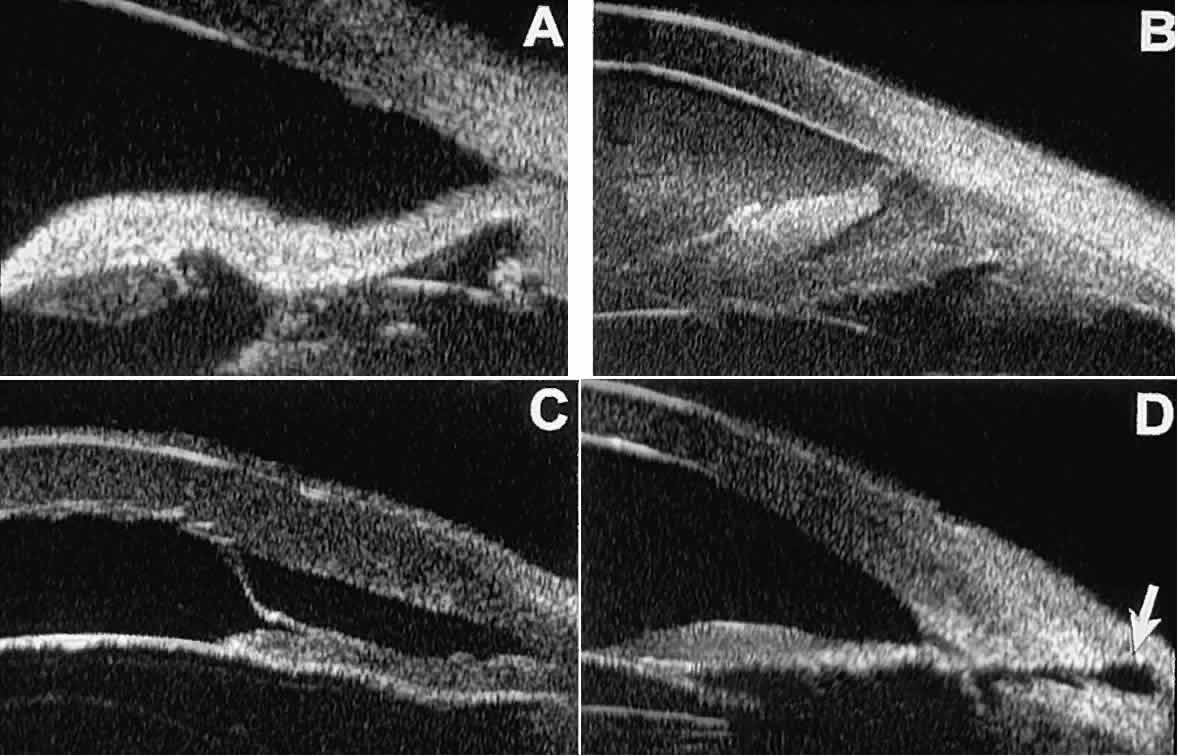

Ultrasound biomicroscopy appears to be helpful postoperatively in determining

the extent of postoperative complications of cataract surgery such

as serous choroidal detachment (see Fig. 13A), iridocapsular adhesion (Fig. 19A), postoperative hyphema (see Fig. 19B), stripping of Descemet's membrane (see Fig. 19C), and wound gaping (see Fig. 19D).  Fig. 19. Complications of cataract surgery revealed by UBM. A. Capsular adhesion to midzone of iris. B. Postoperative hyphema. Clot appears denser than aqueous with suspended

blood cells. C. Stripping of Descemet's membrane. D. Wound gape. Fig. 19. Complications of cataract surgery revealed by UBM. A. Capsular adhesion to midzone of iris. B. Postoperative hyphema. Clot appears denser than aqueous with suspended

blood cells. C. Stripping of Descemet's membrane. D. Wound gape.

|